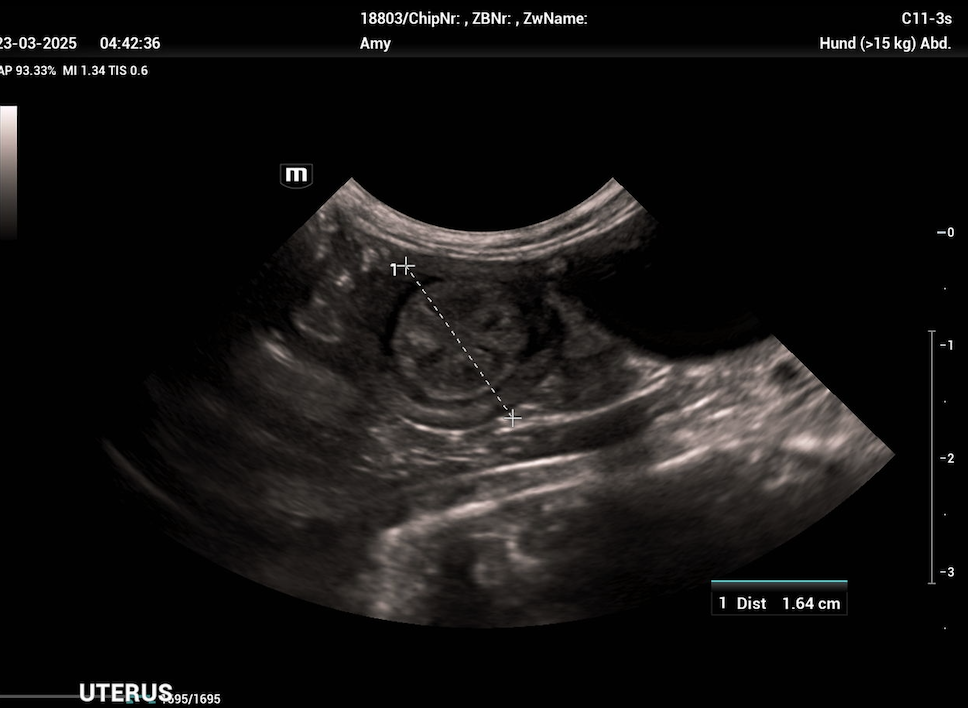

Die Uterusinvolution ist, verglichen mit anderen Spezies, beim Hund ein langsamer Prozess und kann je nach Studie 12 bis 15 Wochen dauernd. Die meisten Rückbildungsvorgänge finden in den ersten 4 bis 6 Wochen post partum statt und in dieser Zeit zeigt die Hündin auch einen geruchlosen, anfangs grünlichen (aufgrund des Uteroverdins der Plazenta) dann eher dunkelroten bis braunen vaginalen Ausfluss, der im Laufe dieser Wochen kontinuierlich abnimmt. Mit diesen Lochien werden Teile der Gebärmutterschleimhaut abgebaut, die aufgrund des epitheliochorialen Aufbaus der Plazenta beim Hund erneuert werden müssen.

Es sollte immer eine (möglichst steril entnommene) bakteriologische Milchuntersuchung inkl. Antibiogramm eingeleitet werden. Weiters können eine Hämatologie und klinische Chemie bei Verdacht auf systemische Beteiligung (Leukozytose, Linksverschiebung, CRP ↑) und ein Ultraschall der Milchdrüse durchgeführt werden. Dieser zeigt bei einer akuten Mastitis nicht mehr von einander unterscheidbare Gewebeschichten. Die entzündeten Bereiche sind echoarm bis echolos und weisen eine grobkörnige Struktur auf. Das Gewebe ist stets heterogen. Bei einer gangränösen Mastitis zeigen sich Zysten mit echofreiem Inhalt und das Zentrum der Entzündung ist von jeglicher Blutzirkulation abgeschnitten (Trasch & Wehrend, 2008). Das Vorhandensein echoarmer, mit Flüssigkeit gefüllter Taschen im Brustgewebe deutet auf eine Abszessation des Brustgewebes hin, während ein hyperechogenes Parenchym auf eine chronische Mastitis hindeutet.